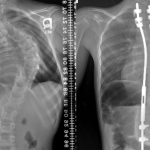

Fiziksel muayene ve tomografi gibi yöntemleri kullanan uzman doktor, kesin tanı konusunda bilgi verecektir. Hasta, başvuru esnasında yaşadığı sıkıntıları detaylı bir şekilde aktarmalıdır. Bilgilere dayanarak elde edilen veriler, görüntüleme teknikleriyle netleşecektir. EMG, MRI gibi yöntemler sinirlerdeki durumu görmek için etkili yollardır.

Sırt fıtığı tedavisinde yaygın şekilde fizik tedavi, ilaç tedavisi, enjeksiyon tedavileri yer almaktadır. Cerrahi tedaviler, ilerleyen sırt fıtıkları için etkili bir çözüm olabilir. Tedaviler ardından gelen süreçte aynı zorlamaları yapmamak, egzersiz önerilerini rutin şekilde sağlamak gerekir.

Sırt fıtığı şayet omurilik üzerinde ezici bir baskı yaptıysa ameliyatlı tedavi yöntemi gerekecektir. Omurilik baskını azaltan operasyon sayesinde günlük yaşamda önemli farklar olabilir.